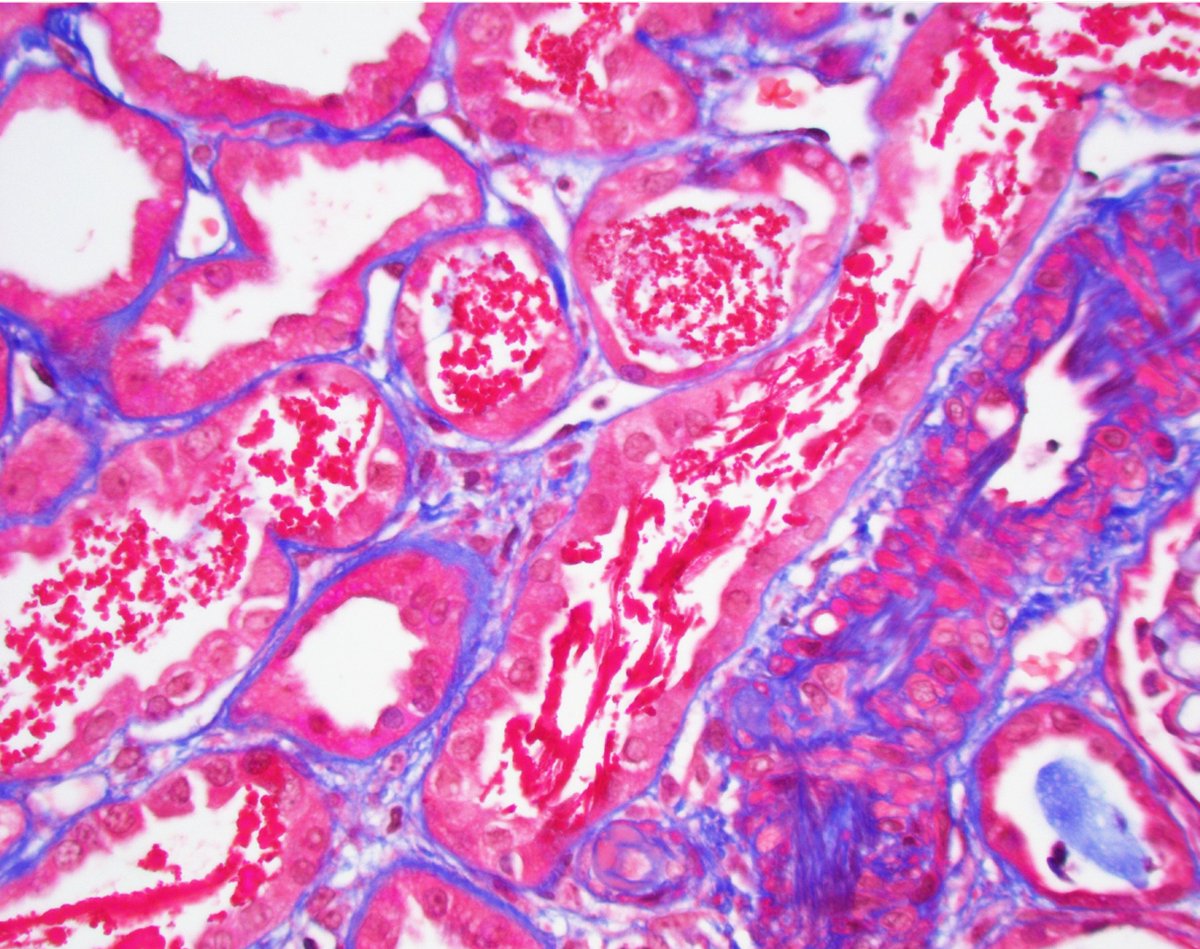

Kidney txp biopsy for AKI (~6 post txp). Tubular injury associated with granular and ropey trichome positive casts. IHC confirmed myoglobin cast nephropathy. CK found to be very high; thought to be due to statin related myopathy. #renalpath #pathwitter #nephrology